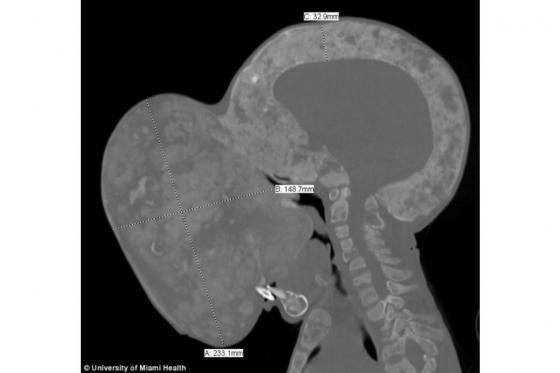

Contenido multimedia principal Fallece Emanuel, el menor cubano que tenía un enorme tumor en el rostro El menor cubano Emanuel Zayas, quien fue operado de un tumor en su cara del tamaño de una pelota de baloncesto, falleció, según confirmó uno de los mé...